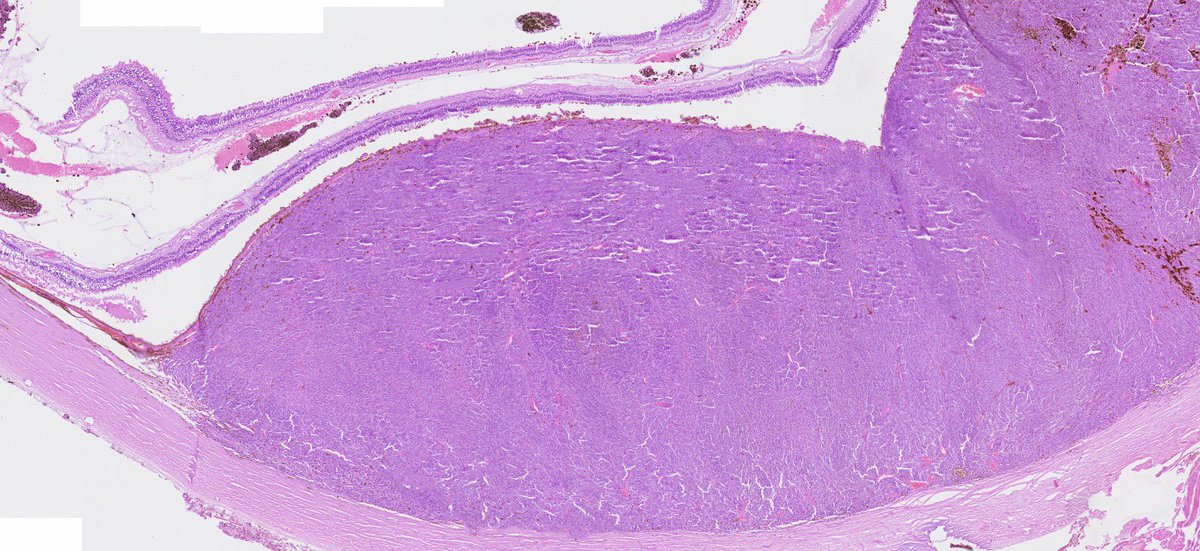

The frozen section